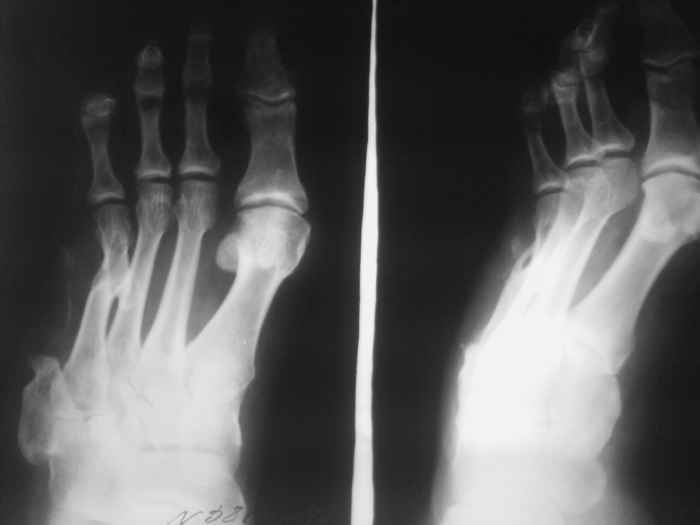

Спасибо за содействие )) В моем случае я не могу точно (без фистулографии, т.к. свищ закрыт) определить уровень и объем резекции кости в соответствии с будущей (надеюсь) операцией для восстановления опороспособности стопы. Или оставшихся трех лучей будет достаточно в ортопедической обуви? Предполагается резекция средней части диафиза 4 плюсневой кости с фистулонекрэктомией.

Можно дождаться открытия свища, дело Ваше, но определяться с объемом операции, по-моему, нужно тщательно.

Не думаю, что потеря еще одного луча добавит опорности стопе. Как Вы планируете после резекции

восстанавливать длину плюсневой кости и добиваться сращения?

Предполагаемый общий (без деталей) план действий за 3тышшы км мне видится таким: 1.санация(нужна ли здесь резекция?),2. спейсер, 3.внешная или диафиксация. Можно добавить для стабильности и опорности на время лечения крепкую пластиковую лонгету на стопу. Кстати спейсер для костной полости не обязательно делать в виде бус.

Лишь бы его можно было легко удалить и в случае необходимости при отсутствии инфекции прибегнуть к костной пластике.